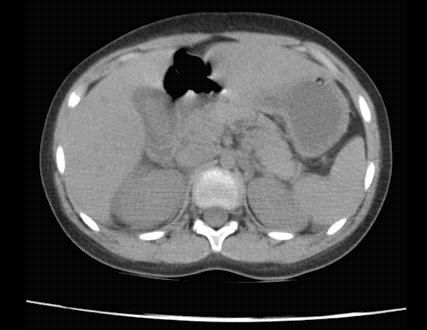

Mientras que dentro del estudio de TAC de abdomen realizado a 13 pacientes el principal hallazgo fue la presencia de líquido perivesicular en 4 (30,76%) de ellos (figura 1 y 2).

Cabe mencionar que ante la duda diagnóstica tanto del pediatra en primera línea como del cirujano pediatra, se realizó estudios de imágenes complementarios tales como ecografía o tomografía de abdomen en determinados pacientes. El principal hallazgo de estas ayudas diagnósticas fueron las alteraciones perivesiculares en el 30% de los casos. Razón por la que sugerimos que ante pacientes con sospecha clínica de apendicitis que presenten clínica o nexo epidemiológico de COVID-19 se considere realizar TAC de abdomen previo al procedimiento. Una revisión sistemática previamente ha reportado que hasta un 34% de los pacientes pediátricos no presentaron ningún hallazgo en tomografía de tórax [18], mientras que en este estudio todos los pacientes mostraron diferentes alteraciones en la imagen pulmonar como se mencionó en los resultados, lo cual podría estar relacionado a las complicaciones que desarrollaron estos pacientes ya sea desde el momento de su ingreso hospitalario o durante la estancia en el mismo.